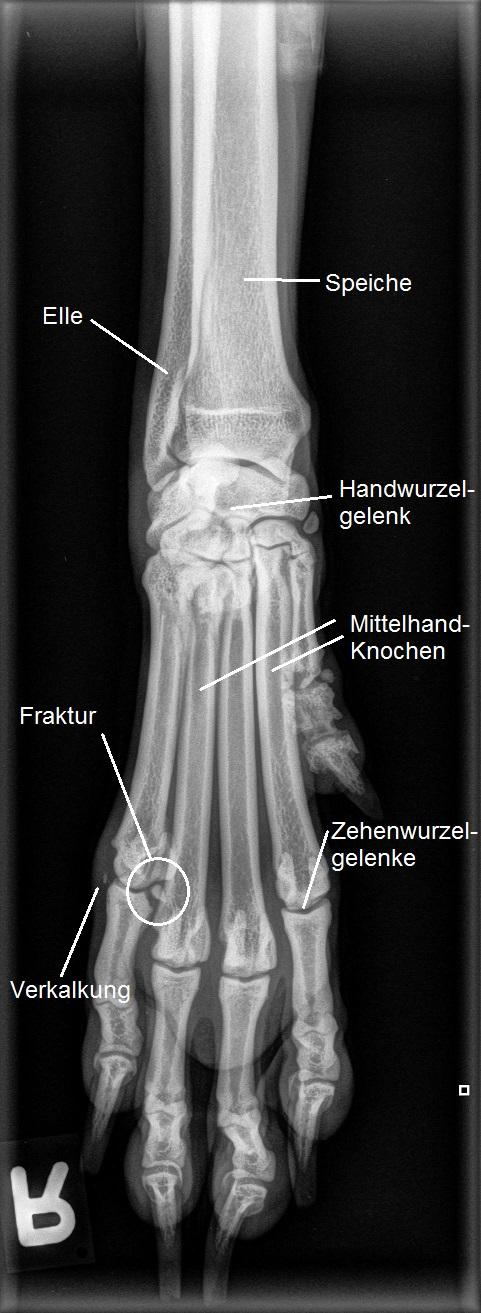

Wir röntgen in Sedation und in absteigender Wahrscheinlichkeit der Lokalisation Ellbögen, Schultern und zuletzt gar die Halswirbelsäule und Handgelenke der Hündin - und finden keinerlei Veränderungen! Schlussendlich fertigen wir noch eine Aufnahme der rechten Vorderpfote an und finden endlich die Nadel im Heuhaufen: Die "Phalanx proximalis Digiti V" (das erste Fingerglied des kleinen Fingers) weist an der Innenseite der Gelenksfläche eine kleine Absprengfraktur auf! Das abgebrochene Stück des Zehenknochens ist mit ca 2.5 x 3 Millimeter winzig. Gleichzeitig findet sich eine kleine Verkalkung im Bereich von Seitenband und Gelenkskapsel des "Fingerwurzelgelenks", welche wohl ebenfalls auf das Trauma am Zehen zurückzuführen ist.

Bei Ivy ist das abgesplitterte Fragment so klein, dass eine Chirurgie nicht zielführend ist. Mit einem Verband wird die Pfote für einige Wochen ruhiggestellt; da es sich um eine Fraktur in die Gelenksfläche handelt, ist es aber möglich, dass das Gelenk nach der Heilung im Laufe der Zeit eine Arthrose entwickeln könnte.